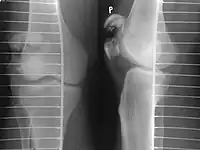

Osteochondral fracture of patella